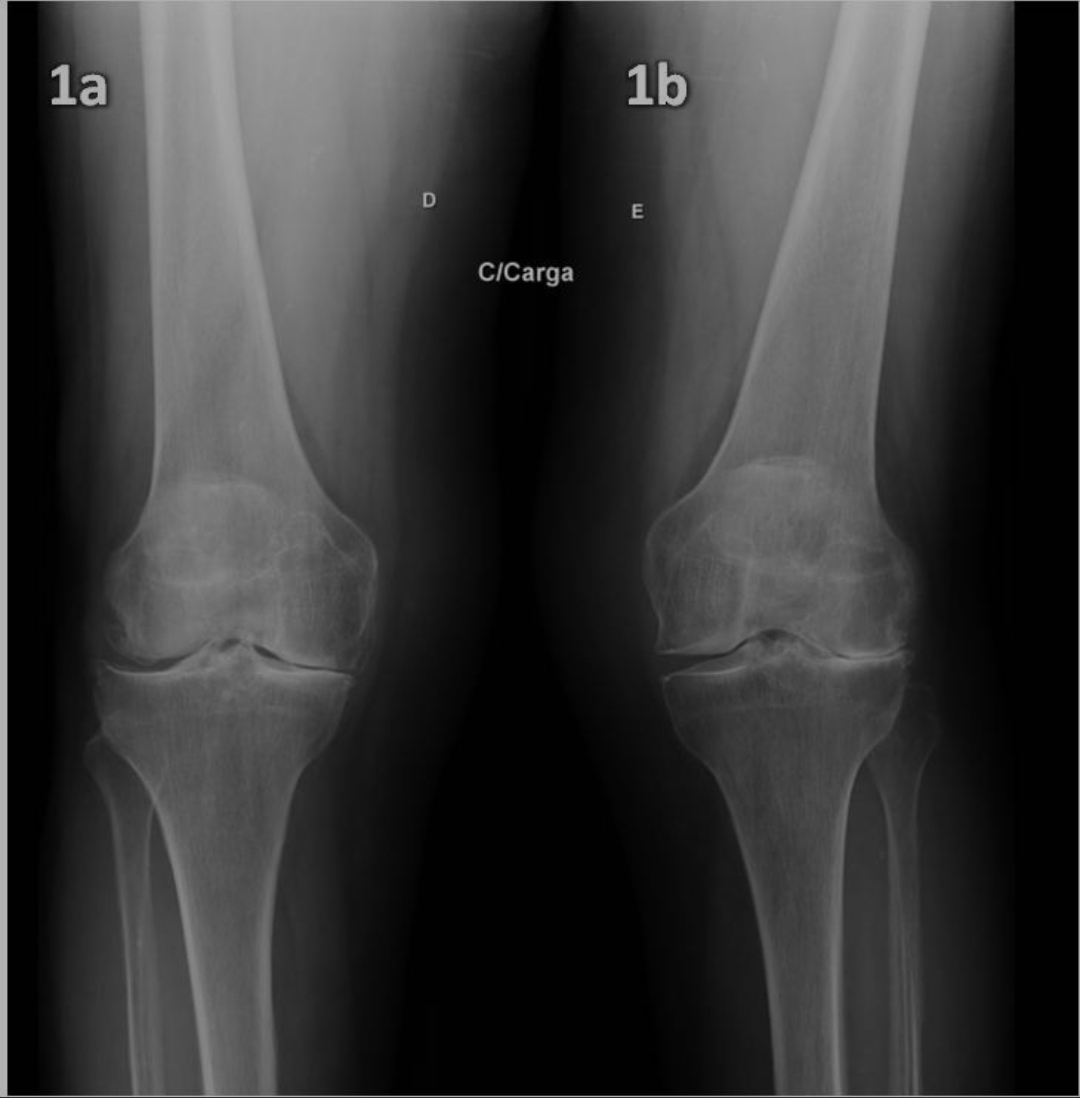

. Raio-X do joelho:

-Avalia alinhamento e sinais de artrose.

-Indispensável principalmente nos casos degenerativos.